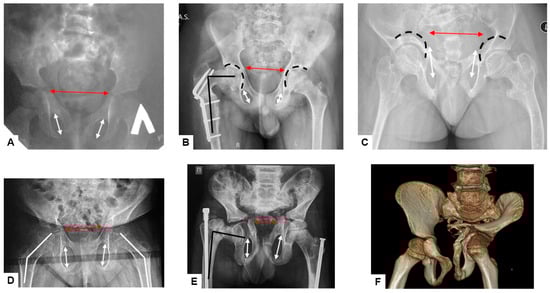

Figure 3. Anteroposterior radiographs of pelvis and hips from patients of the different ages: primary coxa valga (white lines) (D); secondary post-fracture coxa vara (black lines) (B,E); pelvic deformity—narrowing of the anterior part of the pelvic ring (red arrows) (AE); protrusio acetabuli (black broken lines) (B,C); vertically oriented foramina obturatoriae (white arrows) (AE). CT scan of the pelvis and hips (F).